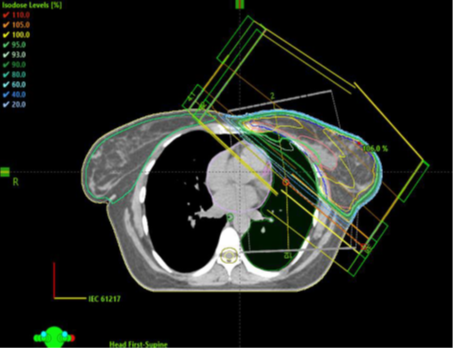

Figur 6. Exempel på dosplan med tangentiella strålfält.

Figur 8. Exempel som visar placeringen av isocenter och CT-snittet för övergången mellan tangentiella strålfält över brösttarget och strålfälten över körteltarget.

Figur 10. Exempel på dosplan med strålfält över bröstkörtelvolymen.